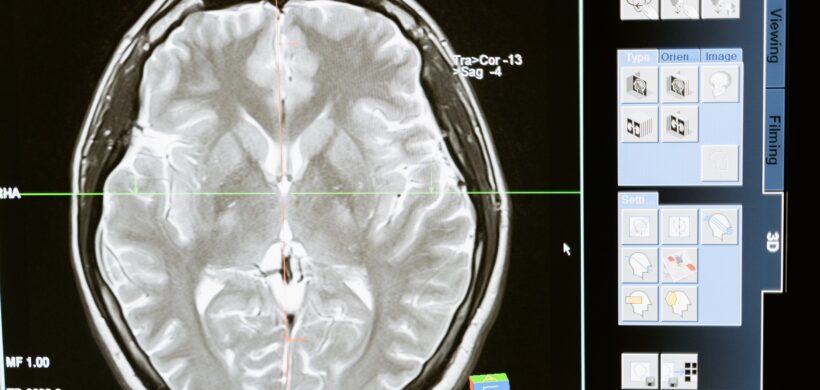

La atrofia cortical posterior (ACP) es una afección progresiva de índole neurológica que genera alteraciones visuales complejas con preservación del estado cognitivo hasta estadios avanzados de la enfermedad. Existe evidencia de compromiso degenerativo de los lóbulos occipitales, parietales y/o temporales posteriores. La ACP es catalogada como una de las variantes atípicas de la Enfermedad de Alzheimer siendo nombrada casi exclusivamente como su “variante visual”. La edad promedio de diagnóstico de esta afección es entre los 50 a los 60 años.

En conclusión, la ACP deberá tenerse en cuenta en pacientes jóvenes adultos que, por lo general ya han realizado múltiples consultas oftalmológicas previas, y que manifiestan alteraciones visuales poco claras pero severas, como la incapacidad para leer o conducir. También en aquellos pacientes donde se evidencia una hemianopsia o cuadrantanopsia homónima en la campimetría computarizada y no se logre identificar en las neuroimágenes lesiones, más allá de la ACP, que justifiquen dicha afección.